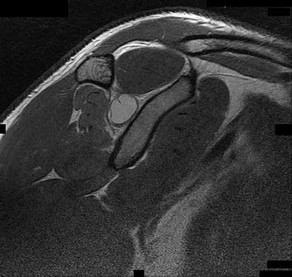

Question 19:

A 55-year-old male is undergoing an arthroscopic rotator cuff repair. A thorough understanding of the anatomic footprint of the rotator cuff is critical for successful anatomic restoration. According to anatomical studies (e.g., Mochizuki et al.), which of the following tendons has the largest insertion footprint on the greater tuberosity?

Options:

- Supraspinatus

- Infraspinatus

- Teres minor

- Subscapularis

- Long head of the biceps

Correct Answer: Infraspinatus

Explanation:

Historically, the supraspinatus was thought to have a larger insertion on the greater tuberosity. However, landmark anatomical studies by Mochizuki et al. demonstrated that the infraspinatus footprint is substantially larger than that of the supraspinatus. The infraspinatus sweeps anteriorly and occupies a significant portion of the greater tuberosity (the lateral aspect), while the supraspinatus insertion is restricted to a much smaller anteromedial area of the greater tuberosity. The subscapularis inserts on the lesser tuberosity.